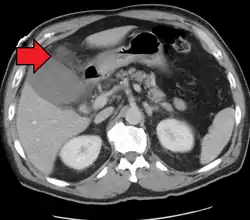

| Acute cholecystitis as seen on CT. Note the fat stranding around the enlarged gallbladder. | |